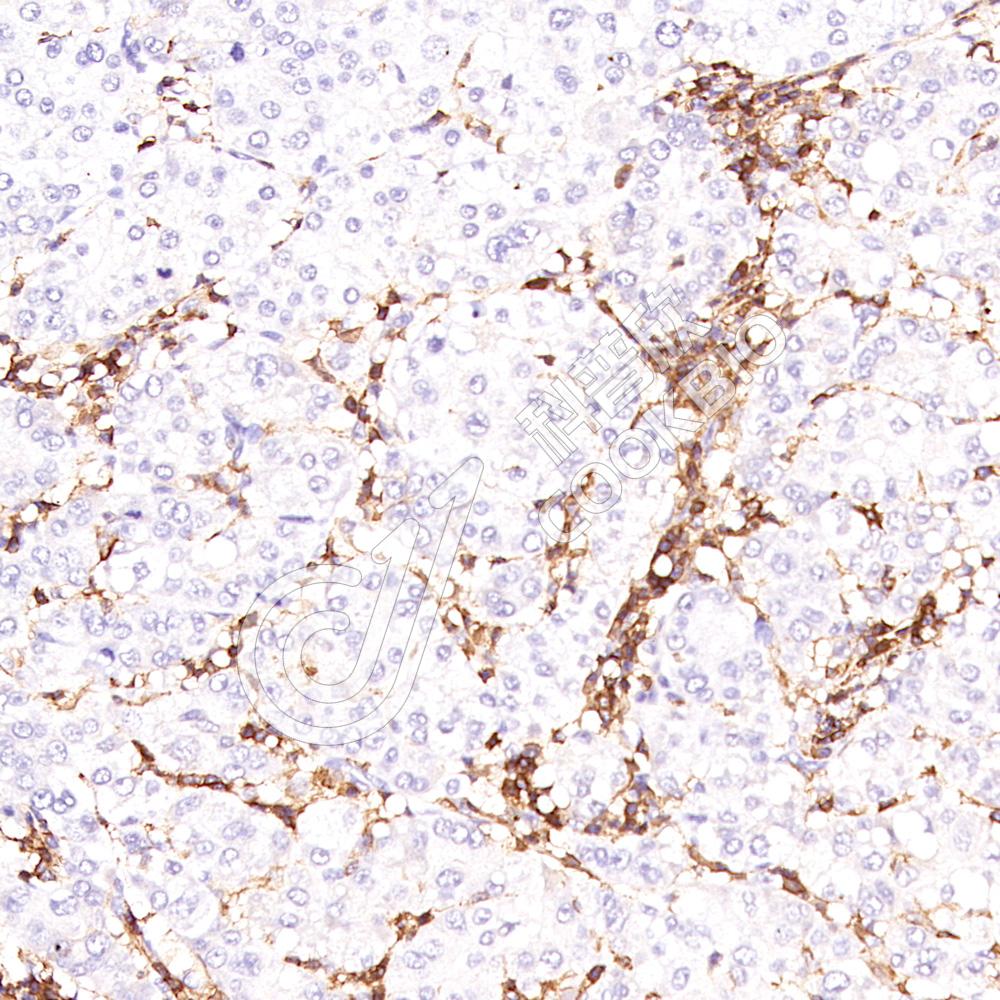

IHC检测CD31蛋白(货号 K133189-2).

样品: 人胎盘, 4%多聚甲醛 (货号KSG1101) 固定12-24小时.

抗原修复: 柠檬酸抗原修复液(干粉, pH 6.0) (KSG1201), 高压锅均匀喷气计时2分钟.

—抗: 1: 700稀释, 4℃ 孵育过夜.

二抗: S-vision免疫组化多聚二抗(山羊抗兔),即用型 (货号KB3906), 室温孵育20分钟.